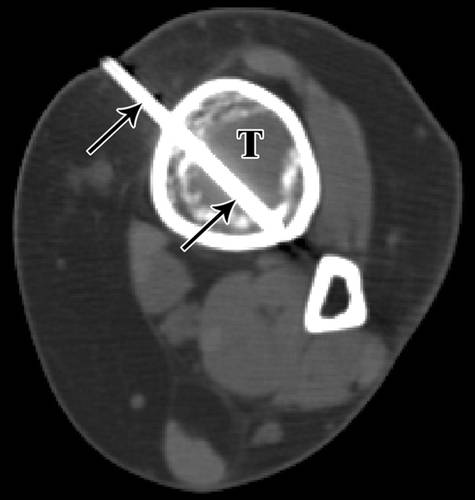

3/ 63岁的男子与I级软骨母细胞瘤。

左肩轴位CT显示肱骨头内硬化病变(H)的11号活检针(箭头)。使用通过三角肌前面部分的前路(D)。